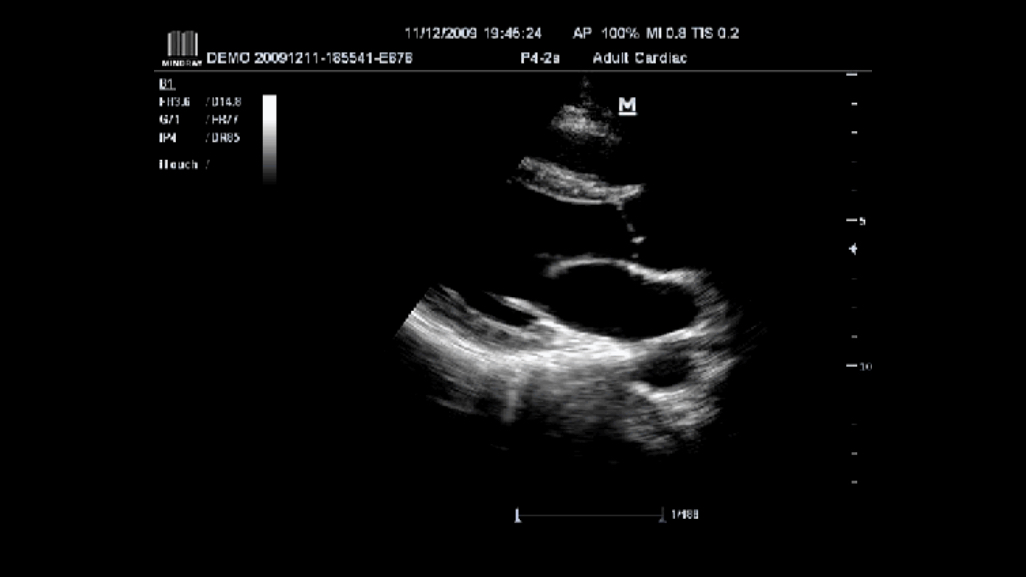

Clinical Images

• p50-s6-1-web

L12-4s iNeedle

• p50-s6-2-web

Brachial Plexus

• p50-s6-3-web

Subscapalaris tendon

• p50-s6-4-web

Long Axis

• p50-s6-5-web

Free Xros